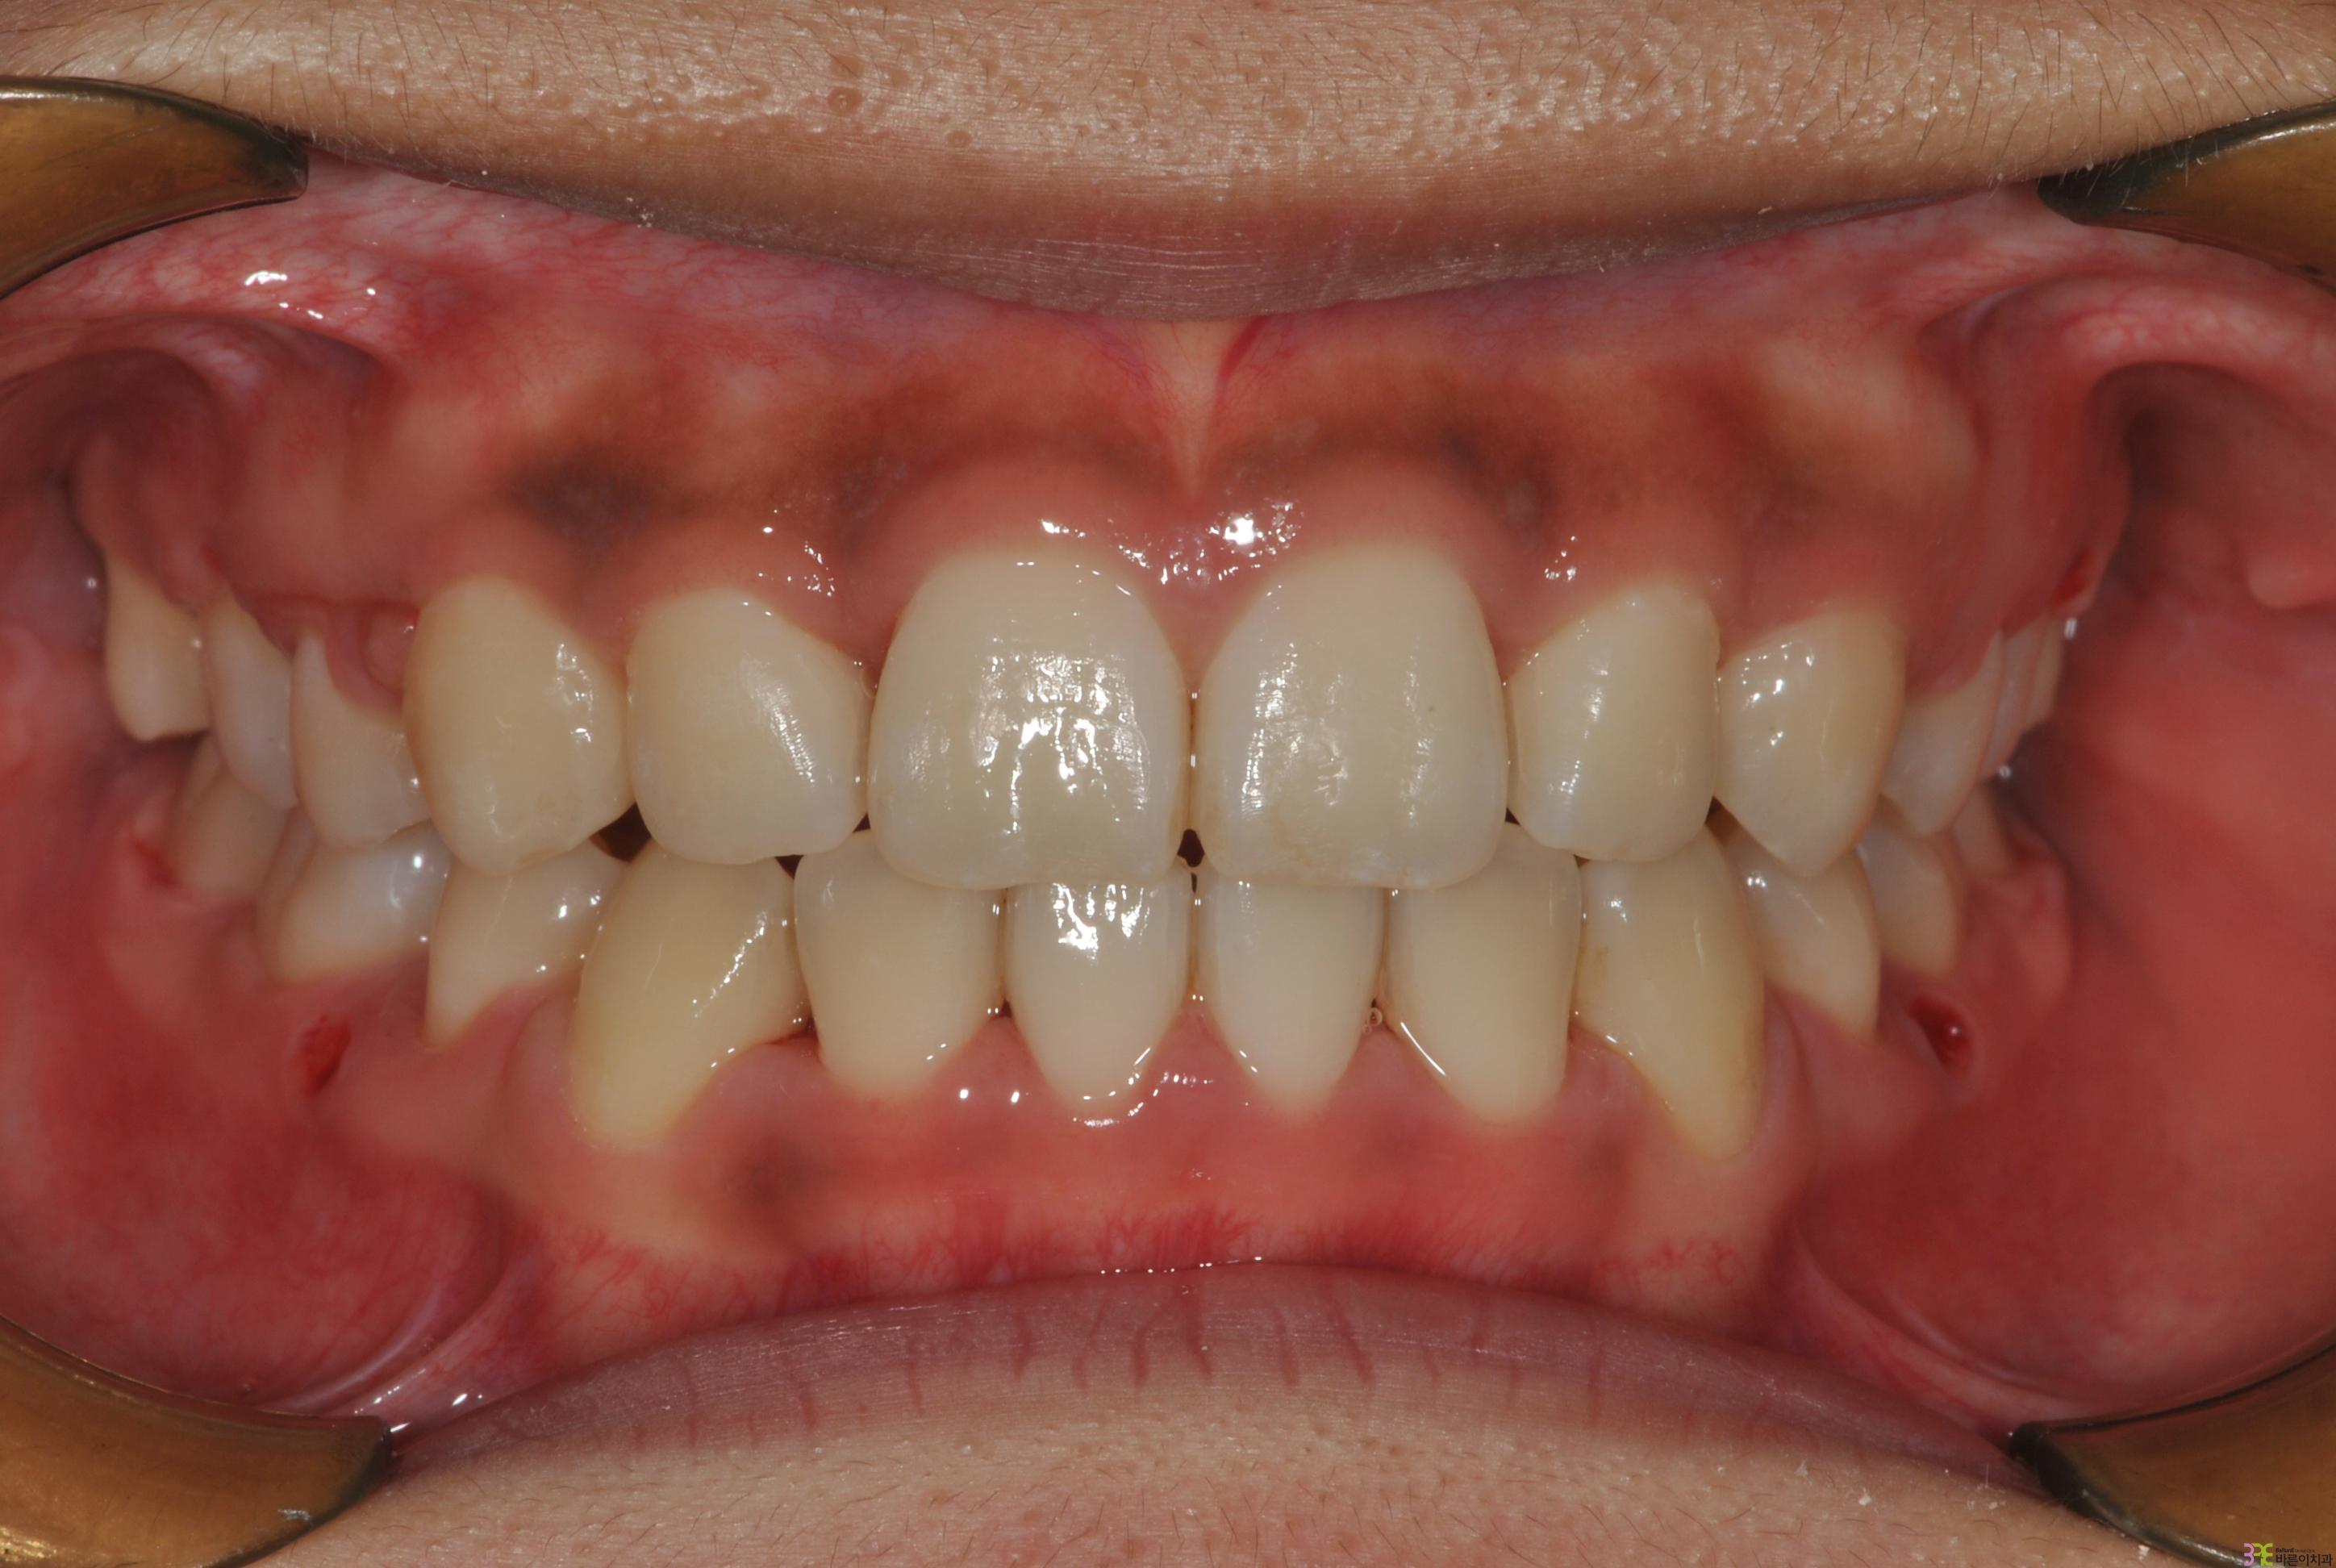

치료명

매복치 교정

치료기간

8개월

Before

After